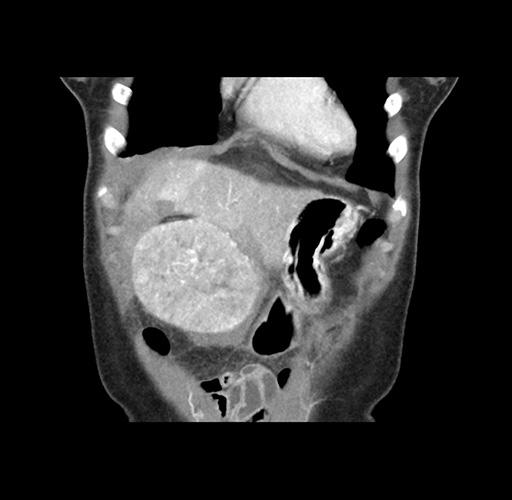

Imaging Analysis

Look through the patient's CT scan to identify any areas of concern for the necessary procedure.

Based on your CT findings, which issue(s) would give reason for "planned slowing down moment(s)" in this case?

Considering a standard left lateral sectionectomy procedure, what step(s) of the operation would you do differently in this case ?